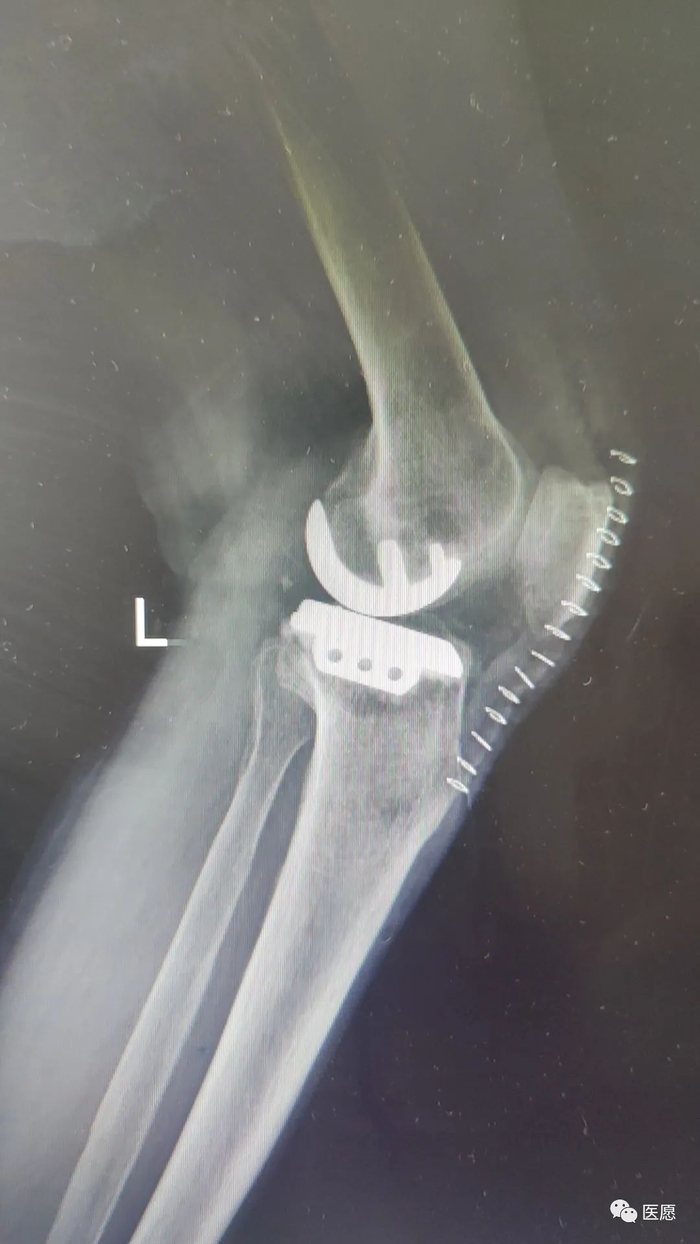

术后片

1

2